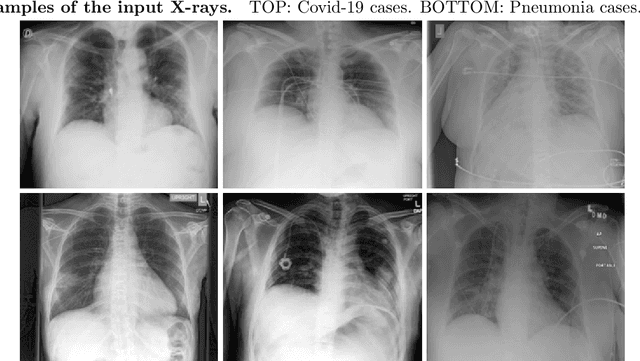

Abstract:Identifying who is infected with the Covid-19 virus is critical for controlling its spread. X-ray machines are widely available worldwide and can quickly provide images that can be used for diagnosis. A number of recent studies claim it may be possible to build highly accurate models, using deep learning, to detect Covid-19 from chest X-ray images. This paper explores the robustness and generalization ability of convolutional neural network models in diagnosing Covid-19 disease from frontal-view (AP/PA), raw chest X-ray images that were lung field cropped. Some concerning observations are made about high performing models that have learned to rely on confounding features related to the data source, rather than the patient's lung pathology, when differentiating between Covid-19 positive and negative labels. Specifically, these models likely made diagnoses based on confounding factors such as patient age or image processing artifacts, rather than medically relevant information.

Abstract:Testing for COVID-19 has been unable to keep up with the demand. Further, the false negative rate is projected to be as high as 30% and test results can take some time to obtain. X-ray machines are widely available and provide images for diagnosis quickly. This paper explores how useful chest X-ray images can be in diagnosing COVID-19 disease. We have obtained 122 chest X-rays of COVID-19 and over 4,000 chest X-rays of viral and bacterial pneumonia. A pretrained deep convolutional neural network has been tuned on 102 COVID-19 cases and 102 other pneumonia cases in a 10-fold cross validation. The results were all 102 COVID-19 cases were correctly classified and there were 8 false positives resulting in an AUC of 0.997. On a test set of 20 unseen COVID-19 cases all were correctly classified and more than 95% of 4171 other pneumonia examples were correctly classified. This study has flaws, most critically a lack of information about where in the disease process the COVID-19 cases were and the small data set size. More COVID-19 case images will enable a better answer to the question of how useful chest X-rays can be for diagnosing COVID-19 (so please send them).